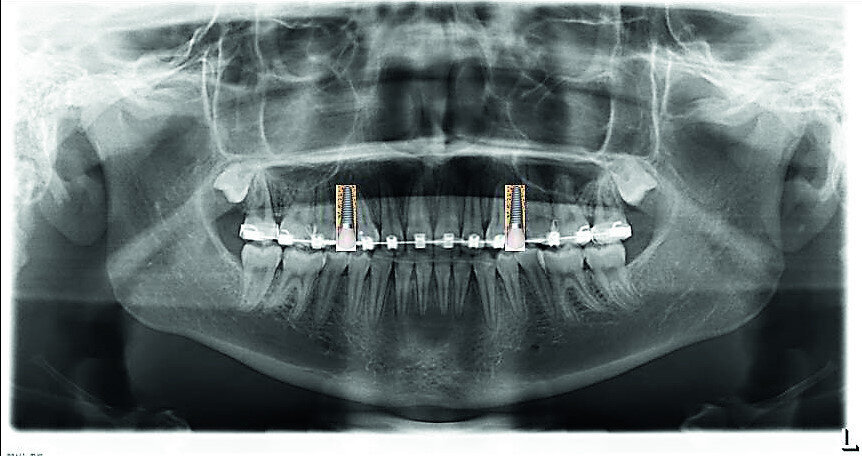

- Open spaces for two implants, but in the posterior area: 14 and 24.

- Temporary implants and crowns on teeth #14 and 24, until 18 years.

- Verifying the implant site width (Fig. 32) and provisory implants and crowns placement (Fig. 33).